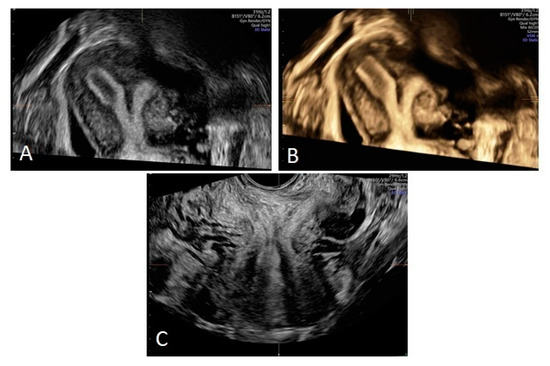

| 17-year-old | 17 years | 13 years | Acute lower abdominal pain, dysmenorrhea | Vaginal mass, pyohematocolpos, pyohematometra | L/L | Laparoscopy, vaginal septotomy, resection of vaginal septum, extension of hemivaginal entry (twice) |

| 13-year-old | 13 years | 12 years | Polymenorrhoea, dysmenorrhea | Vaginal mass, hematocolpos | R/R | Laparoscopy, vaginal septotomy, resection of vaginal septum, extension of hemivaginal entry (twice) |